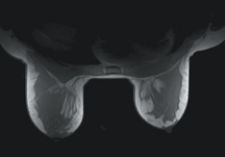

When routinely targeting three and four millimeter lesions, Dr. Causer requires solid compression and a large grid for accessing all quadrants of the breast. “The Vanguard allows us to target lesions in the upper outer and upper inner quadrants of the breast,” noted Dr. Causer, “where other available systems have little or no medial access for biopsy.”

The Vanguard resembles a stereotactic breast biopsy table that allows the technologist to pull breast tissue away from the chest wall. The interventional grids can move both medially and laterally, as well as anteriorly and posteriorly. Glazier uses one hand to hold the breast and the other hand to move the grids and lock them into place. “We can have absolutely no movement of the breast or the interventional grid during our procedures,” said Glazier. “This system is extremely sturdy so we have never had an issue of the grids moving during our procedures.”